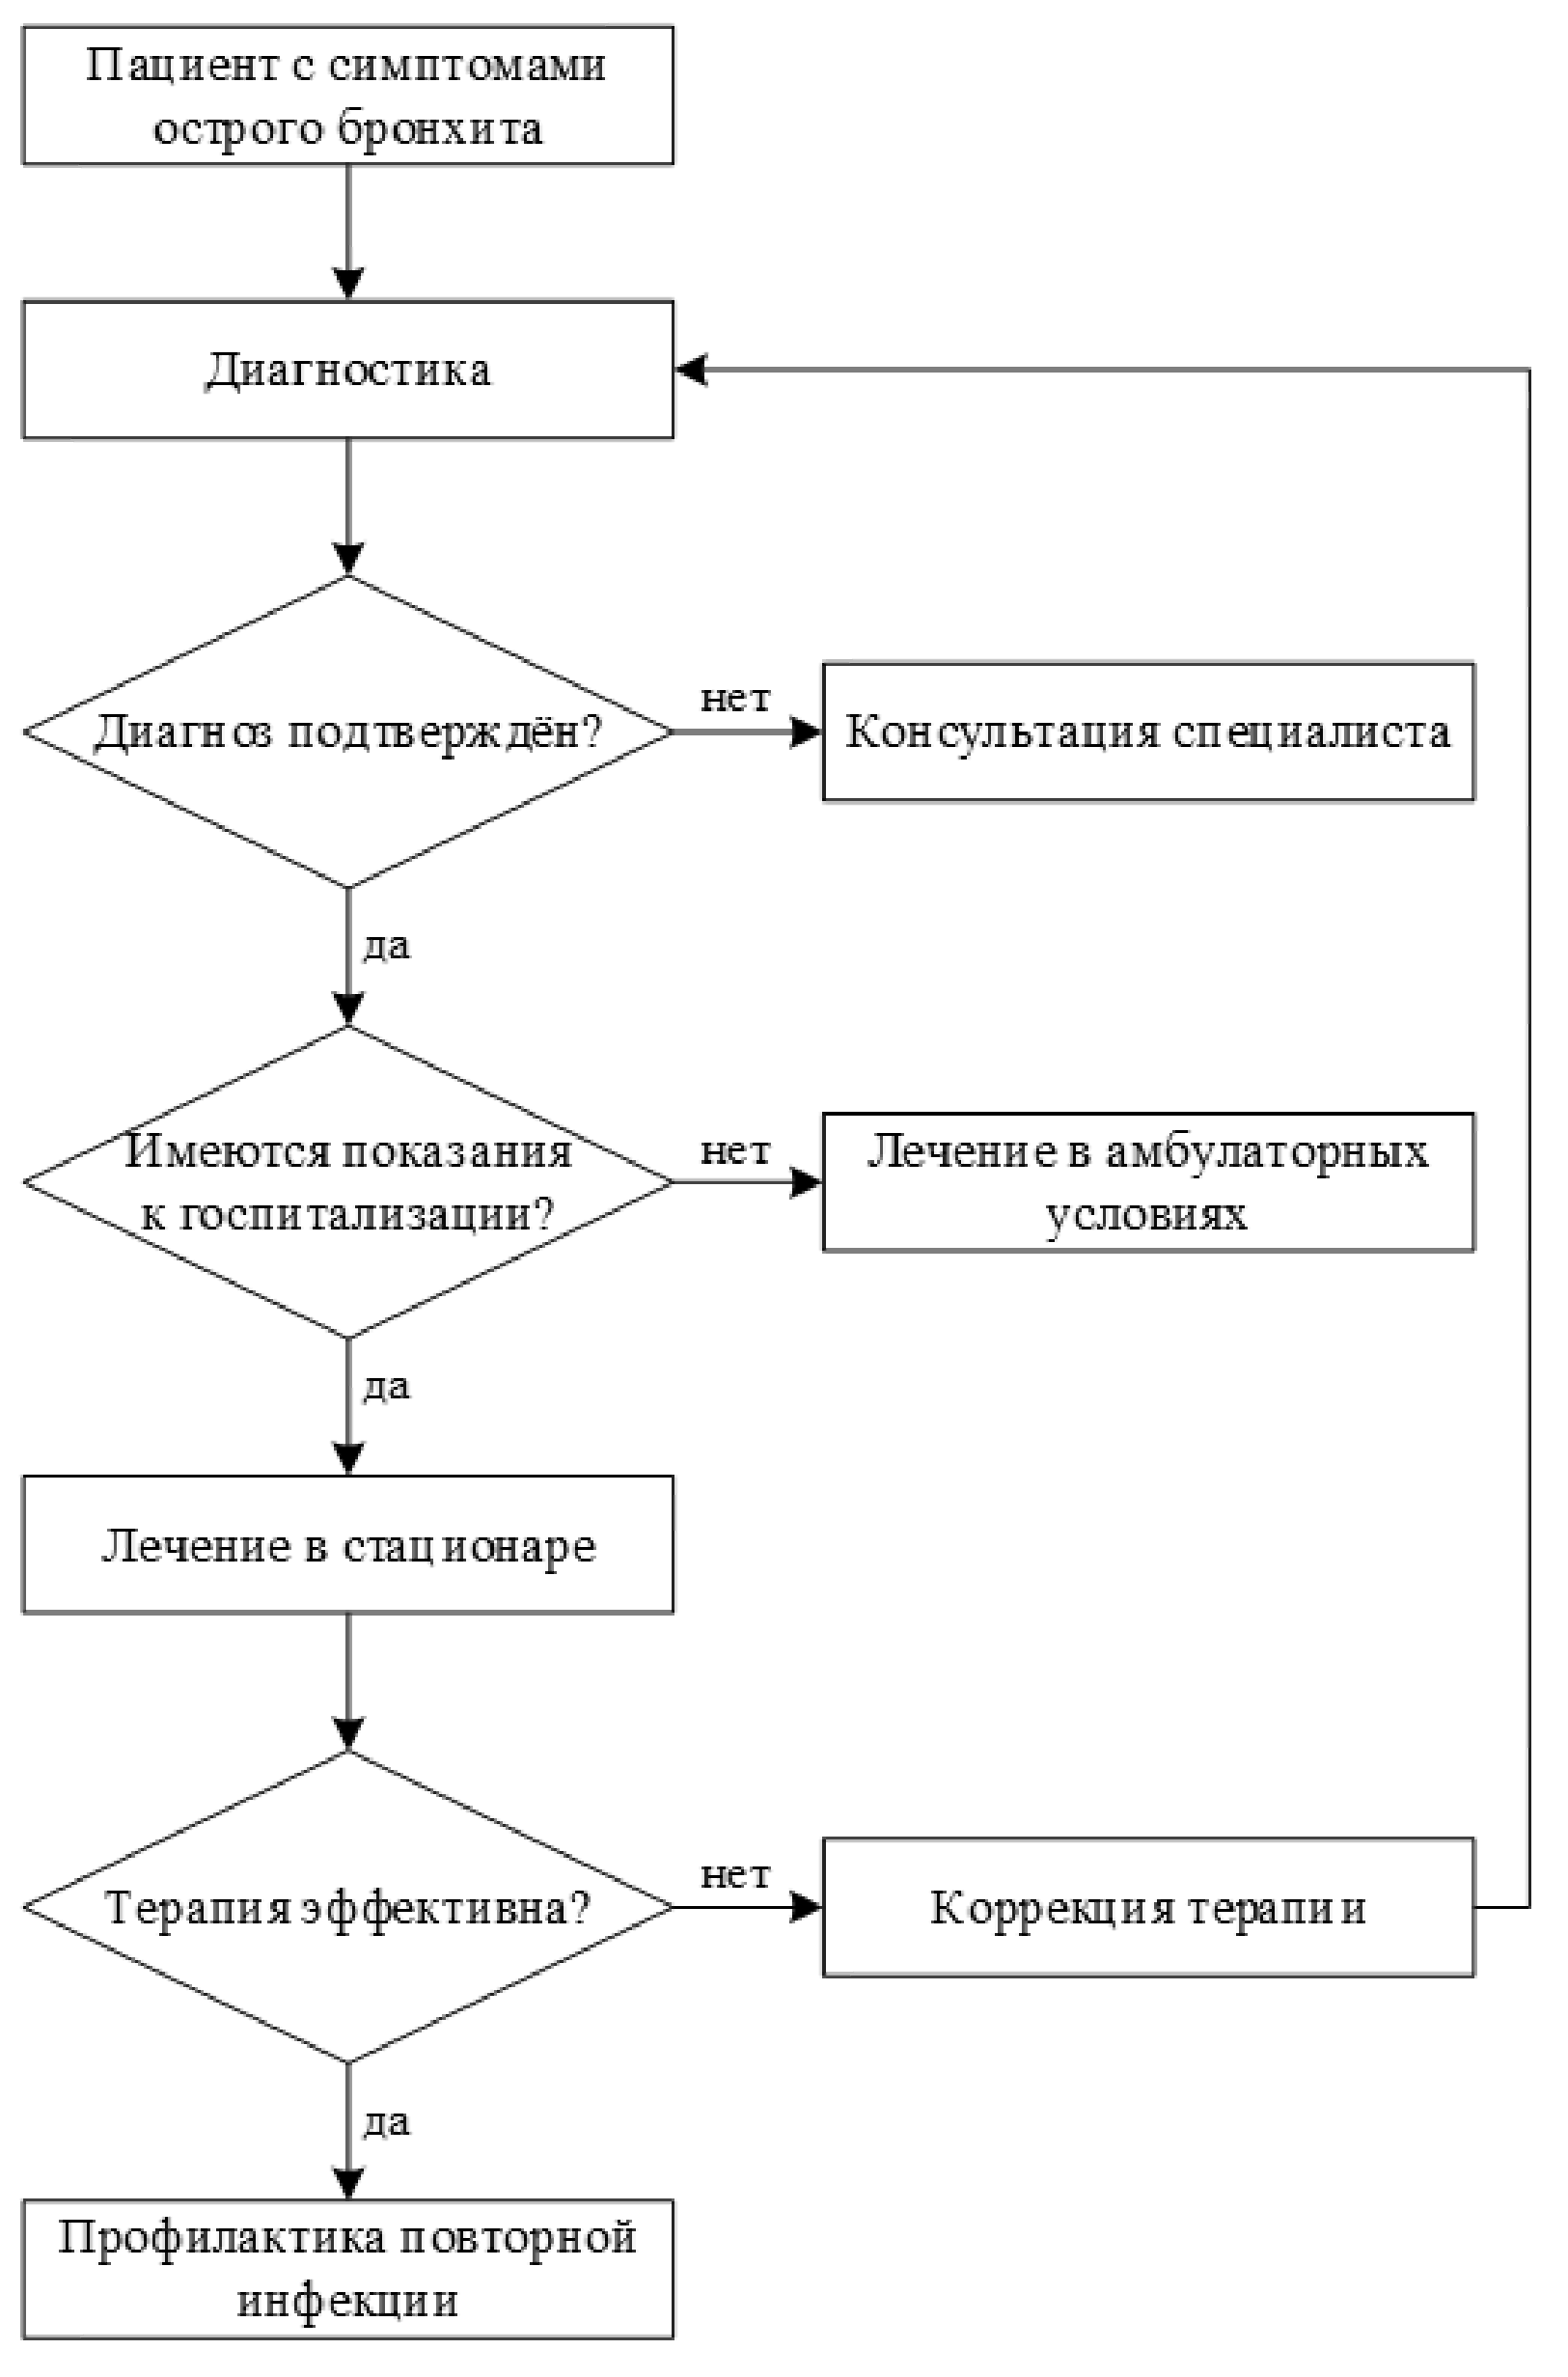

6. Организация оказания медицинской помощи

Острый бронхит обычно требует только амбулаторного лечения (или в условиях дневного стационара).

Госпитализация в круглосуточный стационар при бронхите показана в следующих случаях:

- возраст ребенка младше 3 месяцев (см. клинические рекомендации по острому бронхиолиту);

- вялость ребенка;

- недостаточное поступление жидкости и эксикоз;

- дыхательная недостаточность;

- тяжелая фоновая патология;

- социальные факторы, препятствующие адекватному амбулаторному лечению.

В случае госпитализации пациента с ОБ ребенок может быть выписан домой после купирования лихорадки, дыхательной недостаточности и гипоксемии.

Детей с рецидивами ОБ (а также с затяжным бактериальным бронхитом и хроническим бронхитом) и с обструктивными бронхитами следует направить на консультацию к врачу - аллергологу-иммунологу и (или) врачу-пульмонологу для уточнения диагноза и тактики ведения, при необходимости, обследование и лечение проводят амбулаторно, в дневном стационаре или круглосуточном стационаре.